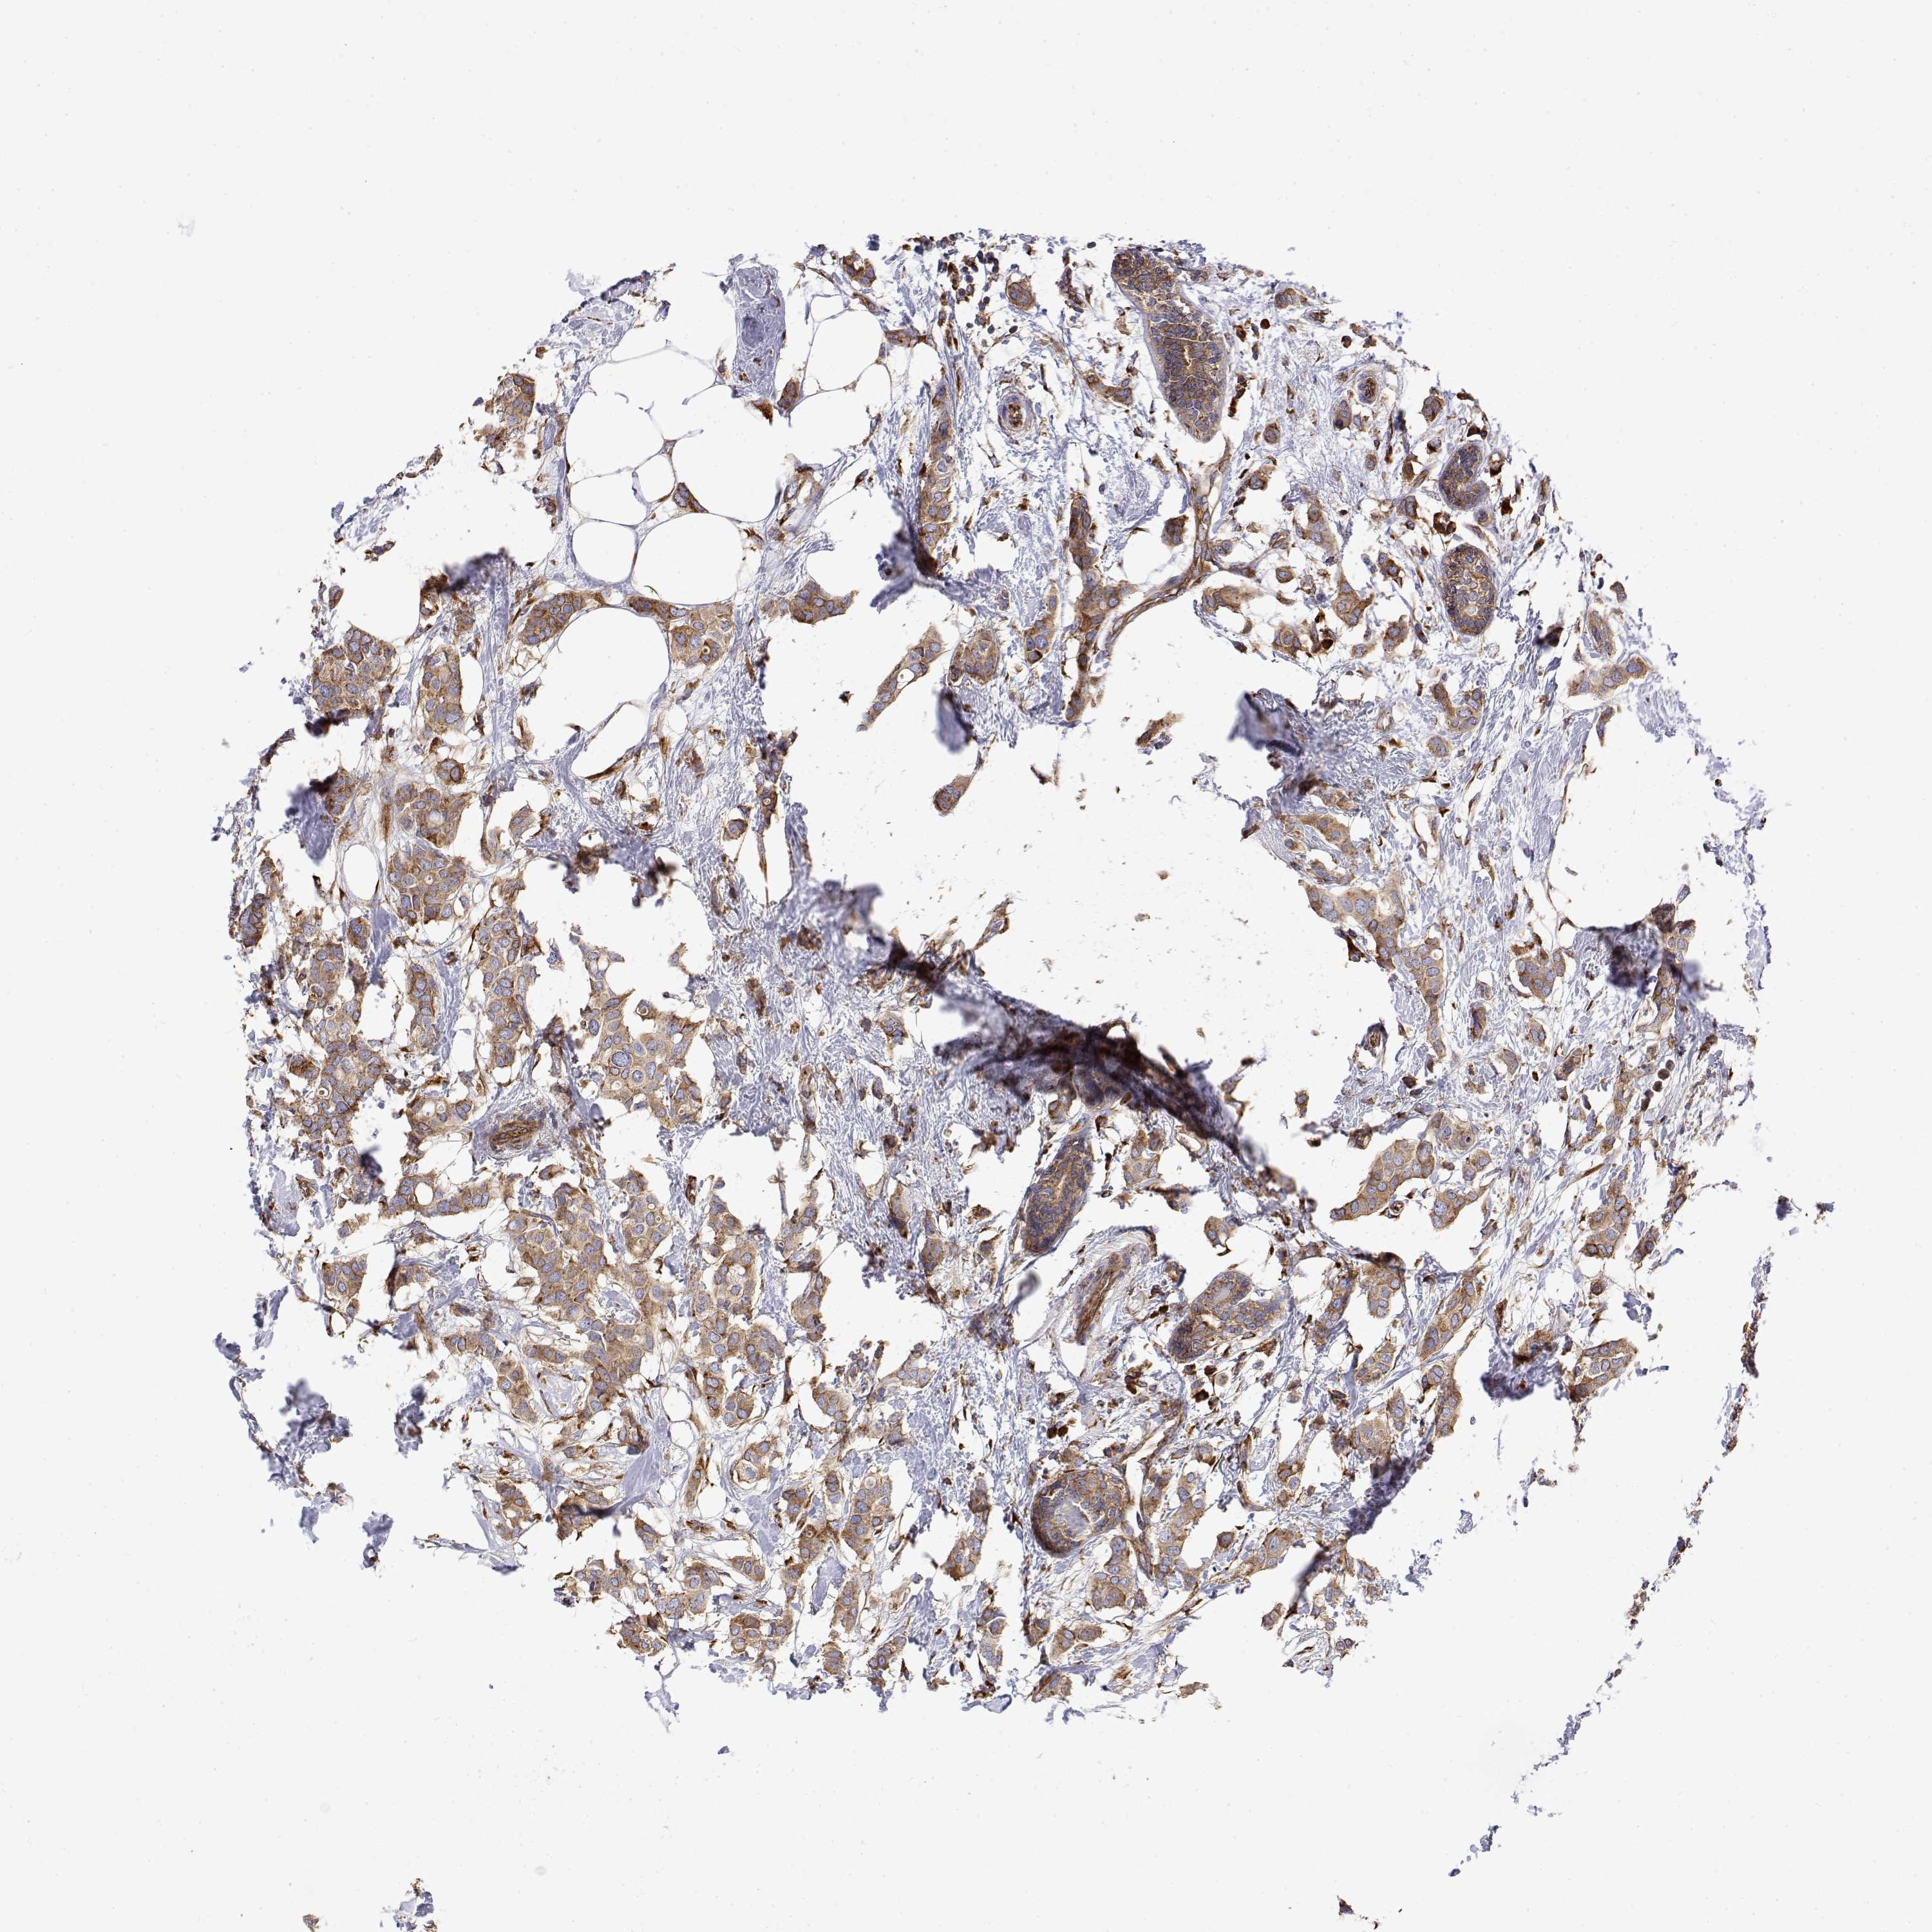

CANCER BREAST CANCER Show tissue menu

BRCA TCGA BRCA VALIDATION PROTEIN EXPRESSION